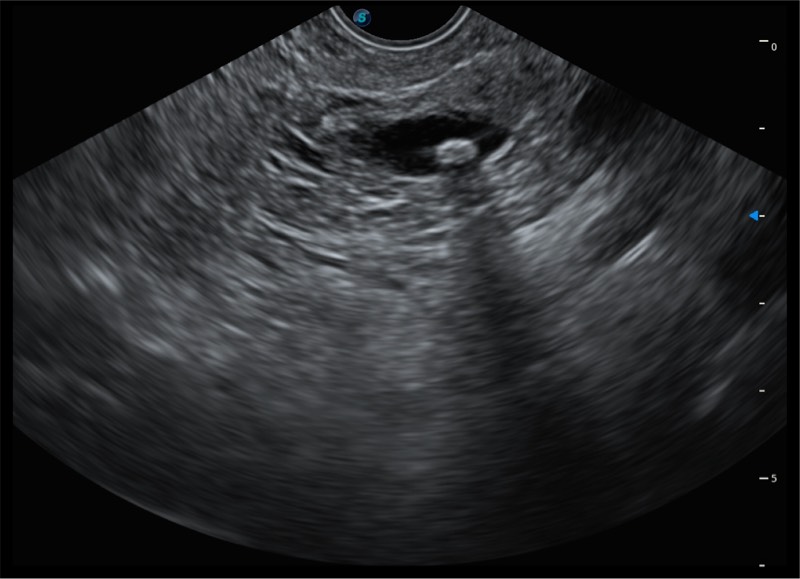

搭载百万级CMOS成像技术

及自主研发凸阵换能器,

可呈现优质的内镜和超声画面

基于二十年的超声技术积累,DB中国旗舰官方网站提供了最新一代的独立超声主机,在提供高质量图像的同时满足多学科使用。具备常见多普勒技术并提供弹性成像、声学造影等高端影像技术。新一代传感器具有更强的抗干扰能力并减少图像伪影。

150°超声扫描角度

4-12MHZ宽频输出